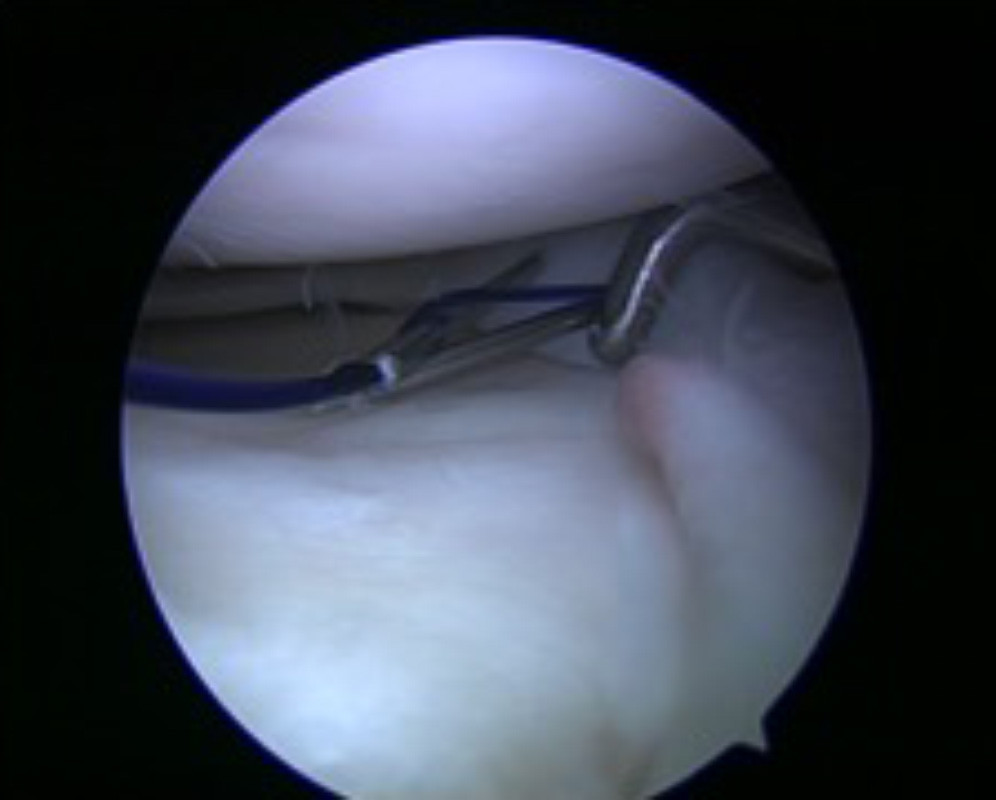

Der Meniskus ist sowohl an seinem vorderen und hinteren Ende fest mit dem Knochen des Unterschenkels verbunden. Diese Fixationspunkte werden als „Meniskuswurzel“ bezeichnet. Zwischen diesen festen Ankerpunkten spannt sich der Meniskus wie ein Trampolin auf und ist hierdurch in der Lage den auf ihn einwirkenden Kräften zu widerstehen. Kommt es zu einer Durchtrennung dieser Aufhängung (Meniskuswurzelabriss „Root Tear“) verliert der Meniskus seine Vorspannung und wird durch den Druck des Oberschenkelknochens aus dem Gelenk herausgedrückt (Extrusion). Hierdurch kommt es zu einem völligen Funktionsverlust des Meniskus ähnlich der Situation nach einer vollständigen Entfernung.

Aufgrund der Seltenheit dieser Verletzung wird sie häufig übersehen. Im Gegensatz zu einem Riss des Meniskus selbst können klassische Nähte die Funktion des Meniskus nicht wiederherstellen. Daher muss das abgerissenen Ende des Meniskus über Knochentunnel und Ankersysteme wieder fest mit dem Unterschenkelknochen verbunden werden. Auch dies kann im Rahmen einer durch einen erfahrenen Operateur im Rahmen einer Gelenkspiegelung ohne langstreckige Eröffnung des Kniegelenkes erfolgen. Nach diesem Eingriff ist eine 6 Woche Entlastung des Beines mit anschließender langsamer Aufbelastung erforderlich, um eine sichere Einheilung zu ermöglichen.

Verletzung der Meniskuswurzel